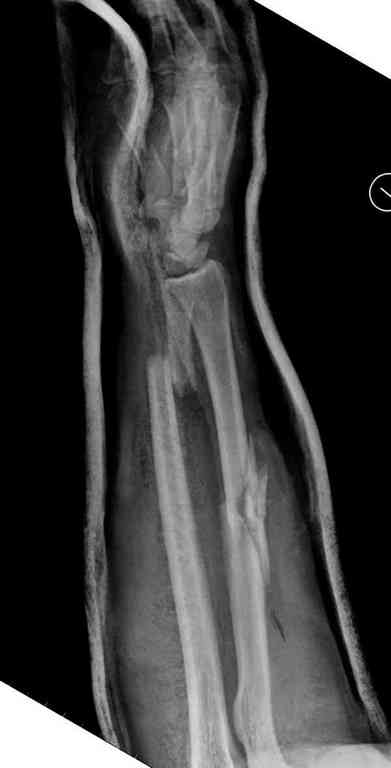

Множественная огнестрельная травма конечностей, перелом костей предплечья, фиксация в первые часы и дефект мягких тканей, мероприятия по закрытию...